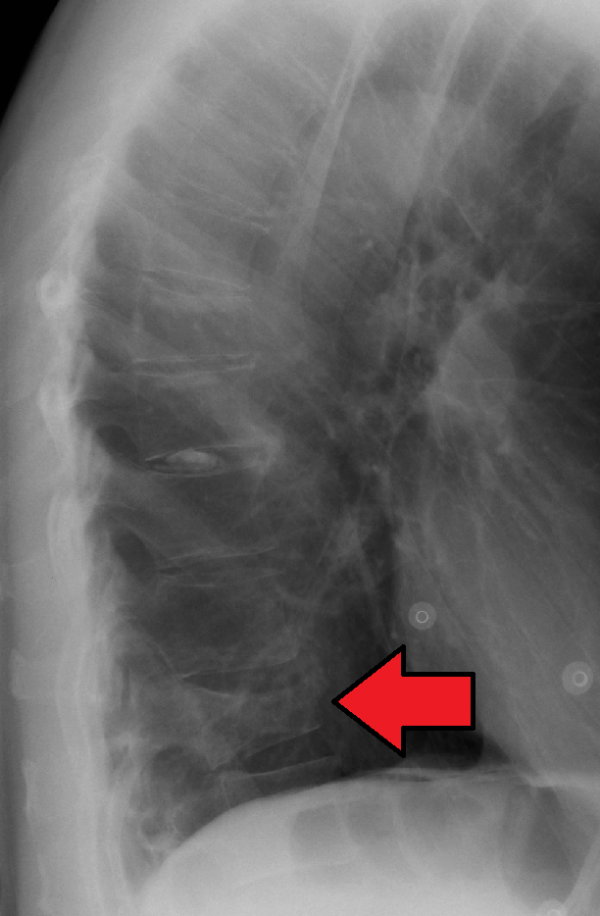

From wikem.org

Thoracic and lumbar compression fractures WikEM Lumbar Compression Fracture Wikem  If the spinal cord or nerves are affected during the fracture, the patient. Thoracic and lumbar compression fractures ; There is a risk of neurological damage, when. Compression fractures are typically diagnosed by lateral radiography of the vertebral column, with or without anteroposterior views. A lumbar compression fracture is a serious injury, both when caused by osteoporosis or by trauma.. Lumbar Compression Fracture Wikem.